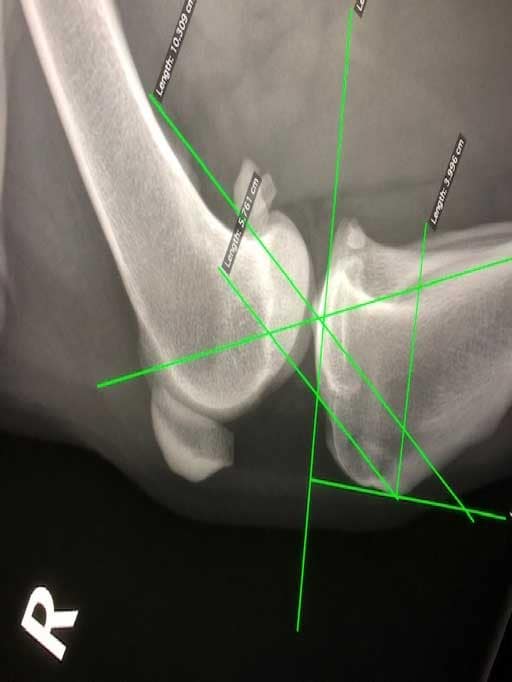

Hieronder links een foto van een gezonde knie en rechts een knie met gescheurde voorste kruisband. Hierbij valt op dat het onderbeen naar voren is geschoven bij de zieke knie.

TTA oftewel Tibial Tuberosity Advancement. De voorkant van het scheenbeen of tibia wordt hierbij ingezaagd en naar voren gebracht. Daardoor gaat ook de aanhechting van de kniepees naar voren.  Om deze verplaatsing te behouden wordt een TTA Rapid kooi geplaatst. Hierdoor veranderen de krachten die werken op het kniegewricht. Het onderbeen zal niet meer naar voren willen gaan, zodat de functie van een kruisband niet meer nodig is. Het goed bezenuwde en pijnlijke gewrichtskapsel staat niet meer op spanning. De knie komt als het ware in rust als de hond er op staat. Met als gevolg dat de knie rust krijgt om te herstellen. Ook komen er geen grote krachten meer op de meniscus in de knie. Eigenlijk maakt de chirurg van de hondenknie een mensenknie. Hiervoor moet er wel in het bot gezaagd en een implantaat met schroeven geplaatst worden. Dit maakt dat deze operatie duurder is dan een Flo techniek. Maar toch is de TTA Rapid goedkoper dan een oudere TTA of TPLO techniek. Hieronder een foto van een TTA Rapid kooi geplaatst in een nepknie.